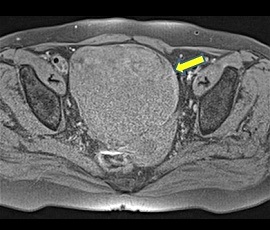

急性腹症にて救急受診。腹部超音波検査にて骨盤内に子宮、膀胱を圧排する約15cm大の辺縁が円滑な単房性腫瘤(矢印)を認め、精査の結果、卵巣腫瘍(矢印)と診断。手術を施行した。病理結果は、成熟嚢胞性奇形腫であった。

MRI画像(脂肪抑制T1強調画像)